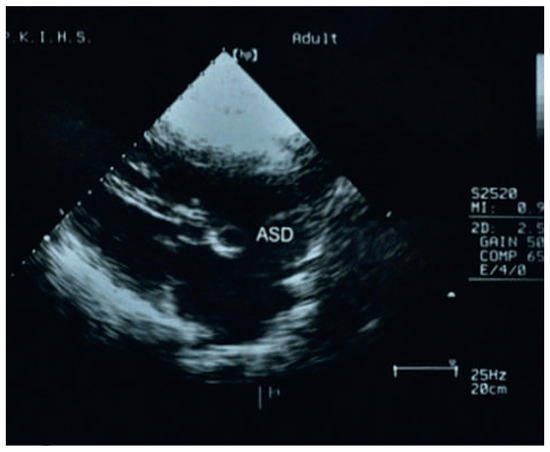

A Family with Upper Limb Malformations and Dyspnoea–The Holt-Oram Syndrome

by Nikesh Raj Shrestha and Stéphane Cook

Cardiovasc. Med. 2012, 15(2), 62; https://doi.org/10.4414/cvm.2012.01649 - 22 Feb 2012

Abstract

A 16-year-old male presented at our outpatient clinic with palpitations and worsening dyspnoea during the preceding five days. [...] Full article

Show Figures

Figure 1